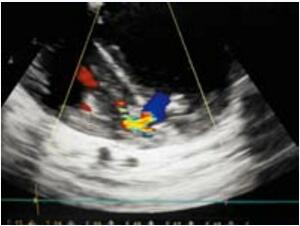

改进也针对复杂解剖的心尖部缺损,笔者称之为“逆向封堵”。虽然病例罕见但是有时会有伴有巨大心尖部壶腹需要较大封堵器方能完成的病例。有时候很值得怀疑这种病人是否能够局部封闭。存在一个缺损隧道,右室肌小梁部存在射流束。隧道方向与右房-右室轴线平行,垂直于右室前壁到缺损之间的轴线,因此根据笔者们的经验穿刺右室前壁通过经典方法穿过缺损极难(图10-48)。如果不改变导丝方向或者在心脏扭曲角度下穿刺前壁将无法通过此类缺损,而且该部位的肌小梁结构可能会不断缠绕导丝,此时由于输送系统是有弹性的,封堵也会受阻。如果遇到此类患者可以通过右房途径进行,切口可在右侧肋间进行。笔者利用一个更简单有效的方式进行。心脏上部拖出切口而不破坏TEE图像暴露室间沟(缺损壶腹部所在),延右室轴线直接穿刺进入通过缺损(图10-49)。而且隧道封堵的完成按照标准方式进行(图10-50)。在提供的病例中笔者选用了一个SQFDQ-Ⅰ14mm的封堵器,封闭了一个2岁患儿 的缺损。值得一提的是,笔者的病人没有任何并发症,没有左室出血危险。在笔者印象中患儿年龄也不比其他方法完成的患者年龄大。